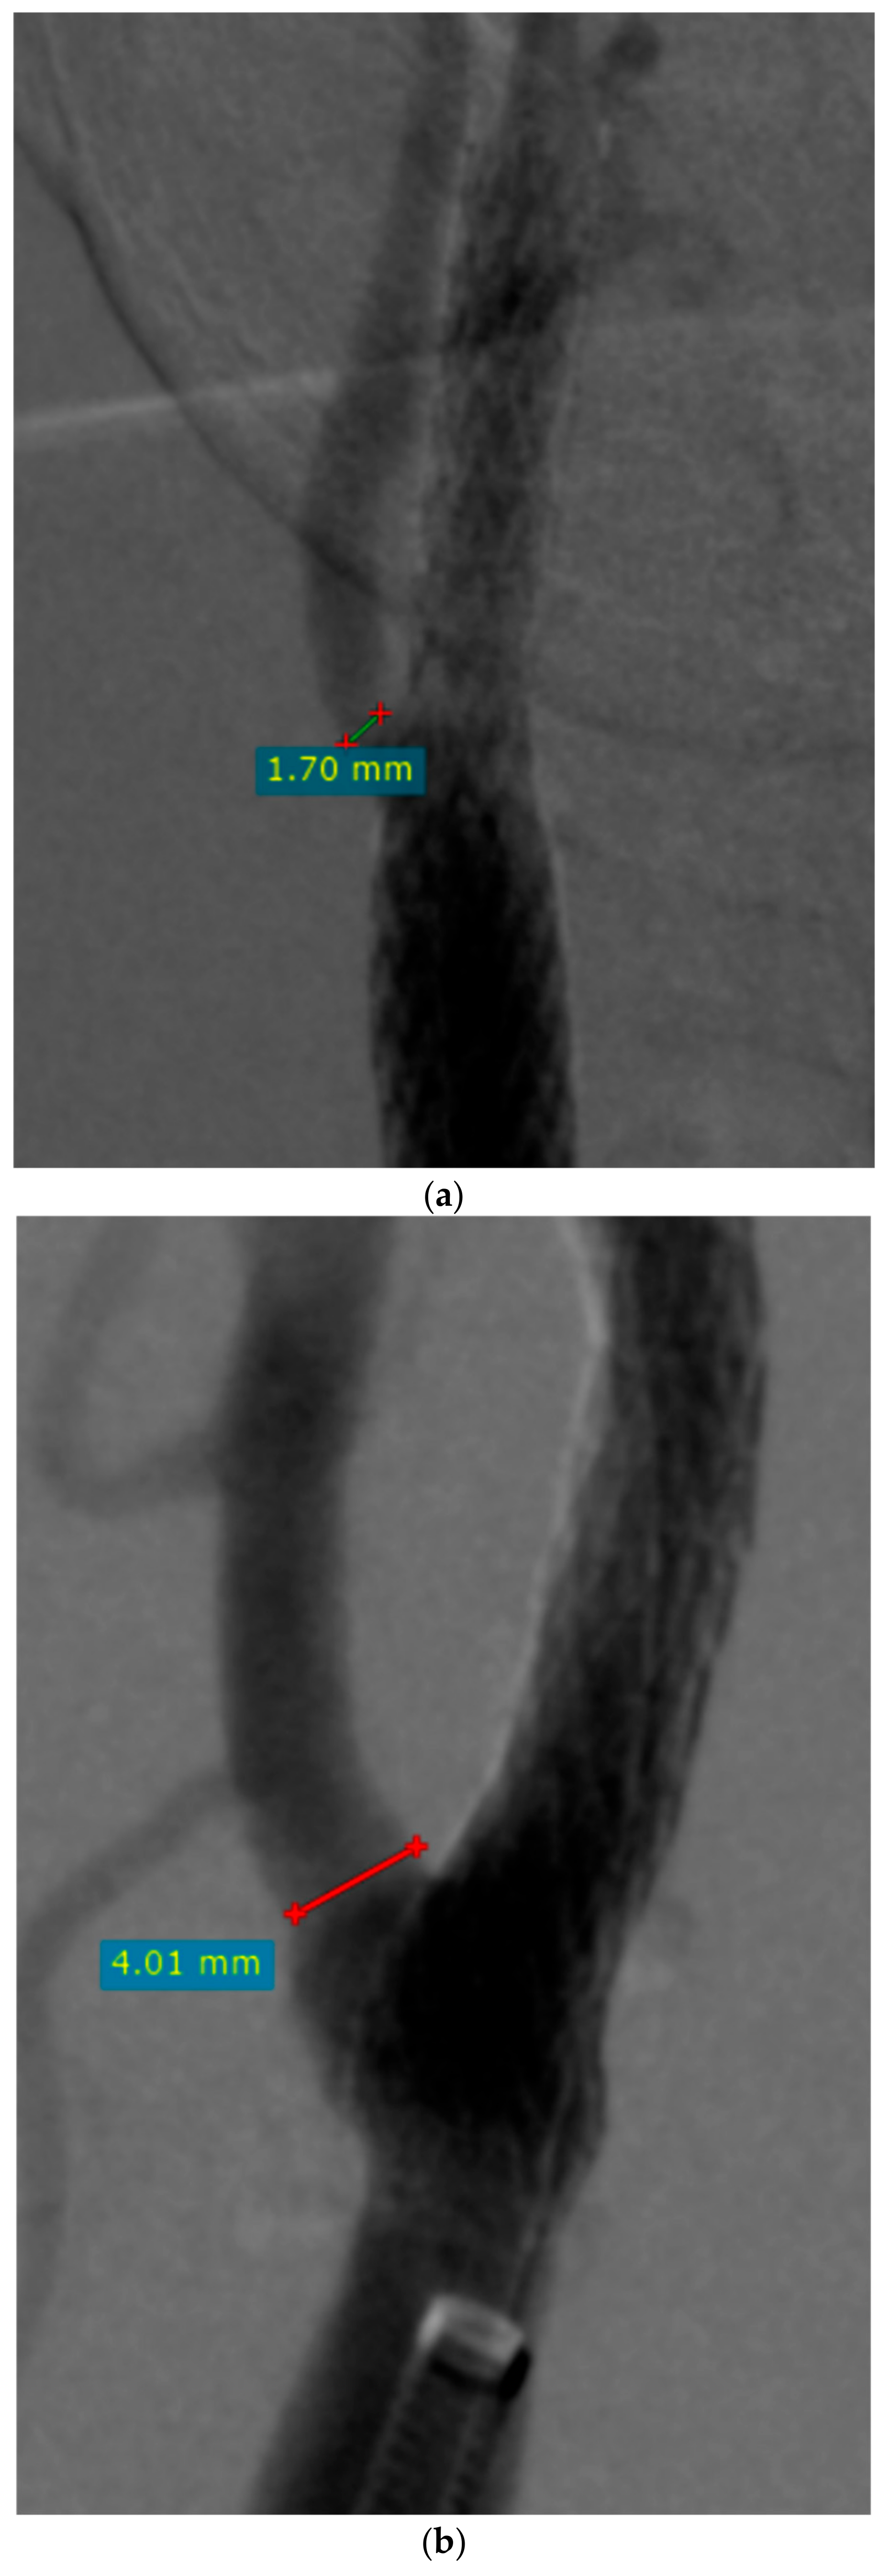

| ECA diameter before CAS (mm) | 4.11 (0–6.84) IQR 1.22 |

| ECA diameter after CAS (mm) | 3.16 (0–5.97) IQR 1.78 |